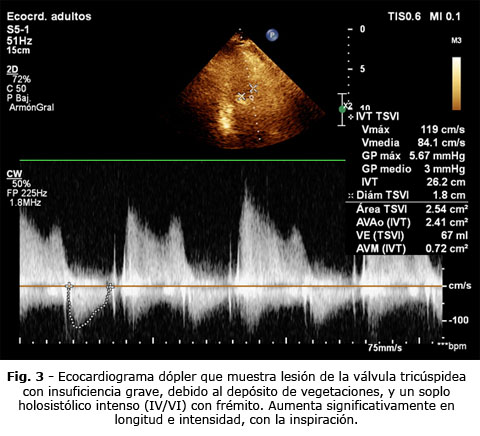

Se decidió hacer algunas investigaciones hematológicas donde se destacó un conteo de leucocitos de 18,6 x109/L a predominio de polimorfo nucleares, stab y células inmaduras; la eritrosedimentación de 148 mm; electrocardiograma con signos de bloqueo fascicular anterior izquierdo (BFAIHH) y signos marcados de hipertrofia ventricular izquierda (HVI). Se comprueba con ecocardiograma dópler a color, presencia de vegetaciones pequeñas, numerosas en todo el ventrículo derecho, con insuficiencia tricúspidea. En cavidades izquierdas aparecen muchas vegetaciones pequeñas; la más llamativa se visualiza en posición aórtica e interfiere en la movilidad de dicha válvula, a la cual está adosada (se ilustran en las figuras 1,2 y 3 estas alteraciones).

Caso clínico: Enfermo con insuficiencia renal crónica, diabético, hipertenso, con catéter venoso central, que presentó, después de una sección de hemodiálisis; escalofríos intensos, fiebre de 39,5 0C, cefalea intensa, toma del estado general, dolor torácico intenso punzante, tos, expectoración con sangre roja rutilante, disnea, soplo regurgitante holosistólico. Se le realizó ecocardiograma dópler que muestra múltiples vegetaciones pequeñas, hemocultivos positivos a estafilococos dorado. Fue tratado según los resultados del antibiograma durante 6 semanas y resolvió su extrema gravedad.